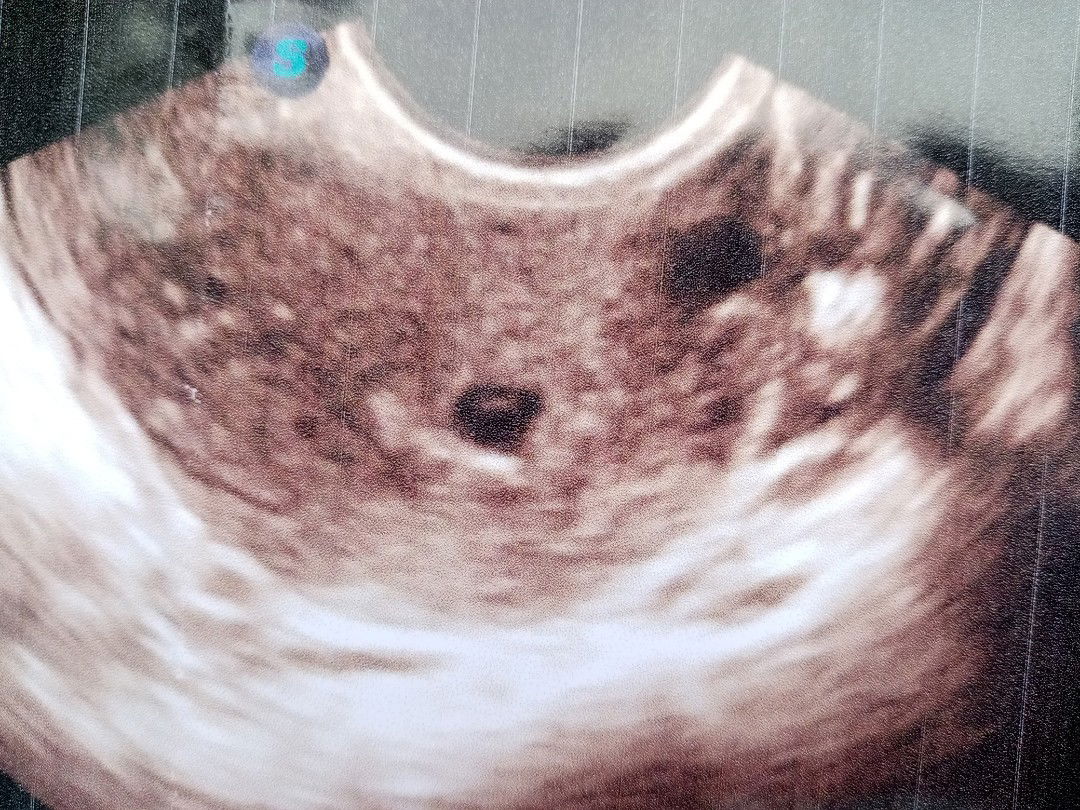

this is mY ultrasound last june 22 .6 weeks and 7 days now via transV 7 weeks and 4 days via lmp.. this is the story. .June 8 nag pt po ako positive then June 18 nag bleedin ako kaya check up agad . nakita sa TransV Na buntis daw ako pero empty sac palang pag Uwe namin natulog ako Pag ka gising ko . umupo ako saglit amy naramdaman akong lmabas skin tpos nag tignan ko buo po siyang dugo .kaya i texted mY Ob kasi baka ung gestional sac ko na un kaya pinabalik ako ng June 22 . and Anjan pa naman daw . is there a chance kaya na mag ka baby pa balik ko plng po july 2 hoping . 3 days lang po pag dudugo ko